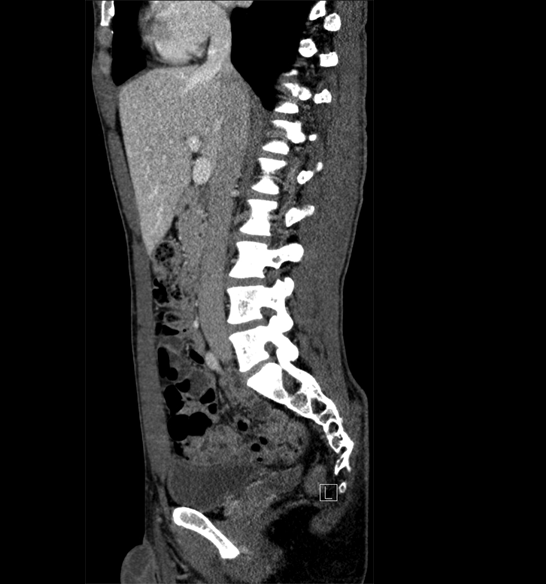

Body

Covers abdominal CT anatomy.